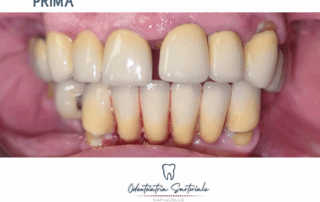

Le faccette permettono di correggere in modo mirato e controllato

Le faccette permettono di correggere forma, proporzioni e colore in modo mirato e controllato. ✨

In questo caso l’obiettivo è stato migliorare l’armonia del sorriso, rispettando denti, gengive e caratteristiche del volto della paziente […]